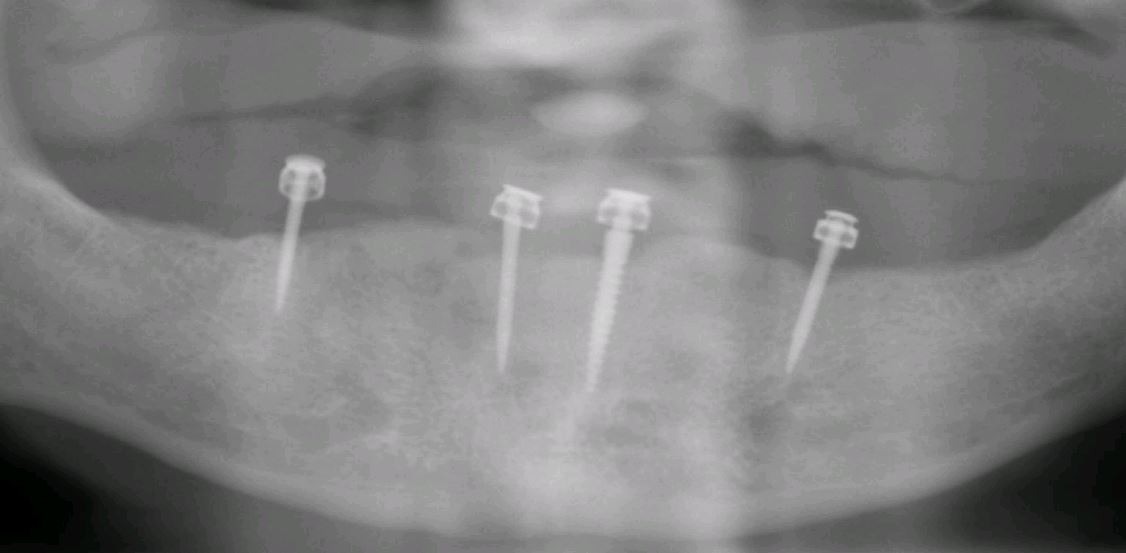

miniimplantate - minimalinvasives implantieren

Vielen Menschen ist nach Jahren oder gar Jahrzehnten der Zahnlosigkeit und dem Tragen von Vollprothesen die Problematik sehr gegenwärtig. Neben dem oft mangelhaften Sitz der Zahnprothesen gibt es immer wieder schmerzhafte Druckstellen, die Sprachbildung ist erschwert und das Zerbrechen dieser Kunstoffzähne ist immer eine Gefahr. Aber gerade ältere Menschen stehen einer operativen Implantatbehandlung skeptisch gegenüber. Sie fürchten die Dauer der Behandlung oder haben Bedenken wegen einer möglicherweise eingeschränkten allgemeinen Gesundheitsverfassung. Hier bietet die minimalinvasive Implantologie Abhilfe. Durch das spezielle Design von sogenannten -Miniimplantaten- kann eine aufwändigere Operation vermieden werden. Das Einbringen dieser Implantate kann dann auch ohne ein chirurgisches Schneiden der Kieferschleimhaut geschehen. Natürlich ist bei diesem minimalinvasivem Vorgehen eine zuverlässige Vermessung mit Hilfe von 3D-Röntgen notwendig um eine genaue Position der Implantate zu erzielen und keine Verletzungen oder Schäden zu verursachen. Auch hier kann bereits am Tag des Eingriffs die gewünschte Verbeserung des Haltes der Prothesen durch die eingearbeiteten Druckknöpfe erreicht werden.